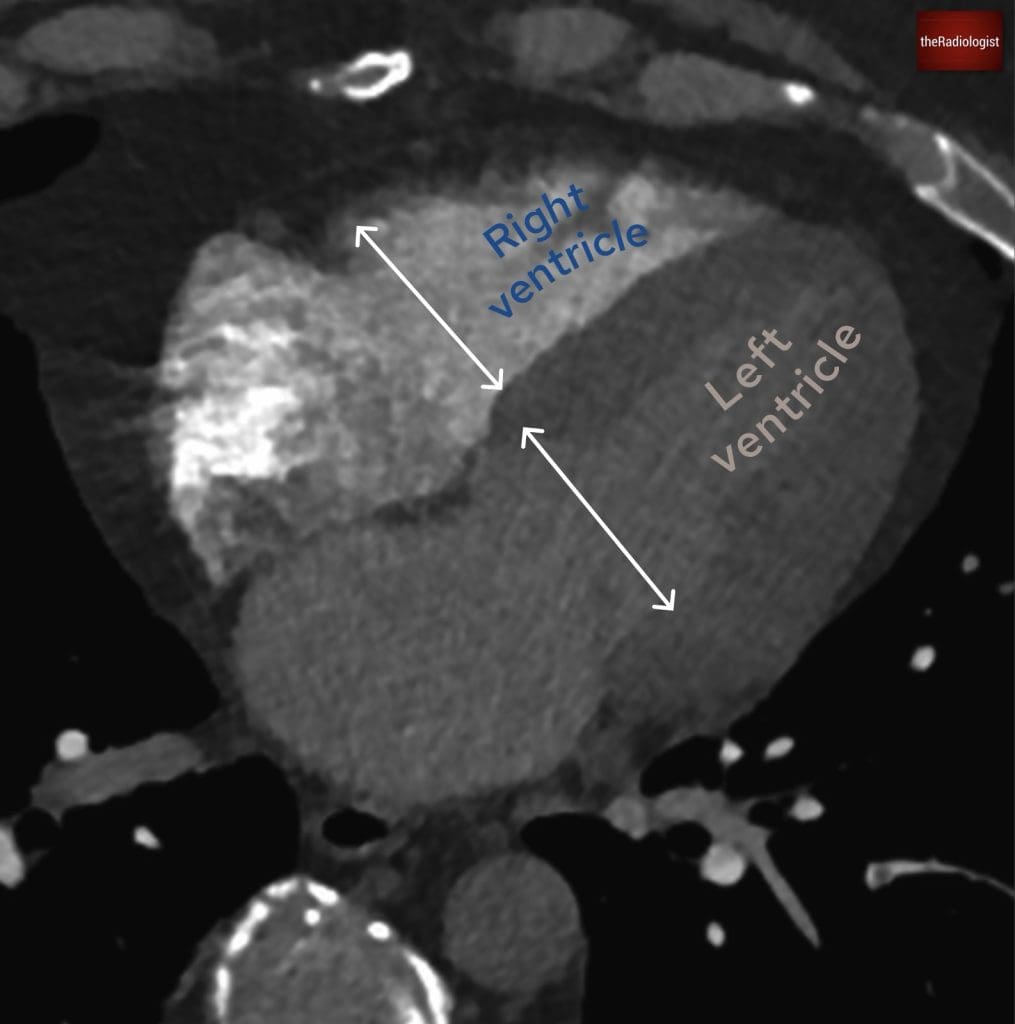

Right heart strain

Signs of right heart strain appear present, with namely an enlarged RV as well as a flattened interventricular septum, and reflux of contrast: all of which raise concern for significant haemodynamic impact. As discussed earlier, these findings correlate with increased 30-day mortality and inform how aggressively the patient might need to be treated.

In this case the RV/LV axial dimension ratio is >1 and we can call right heart strain.